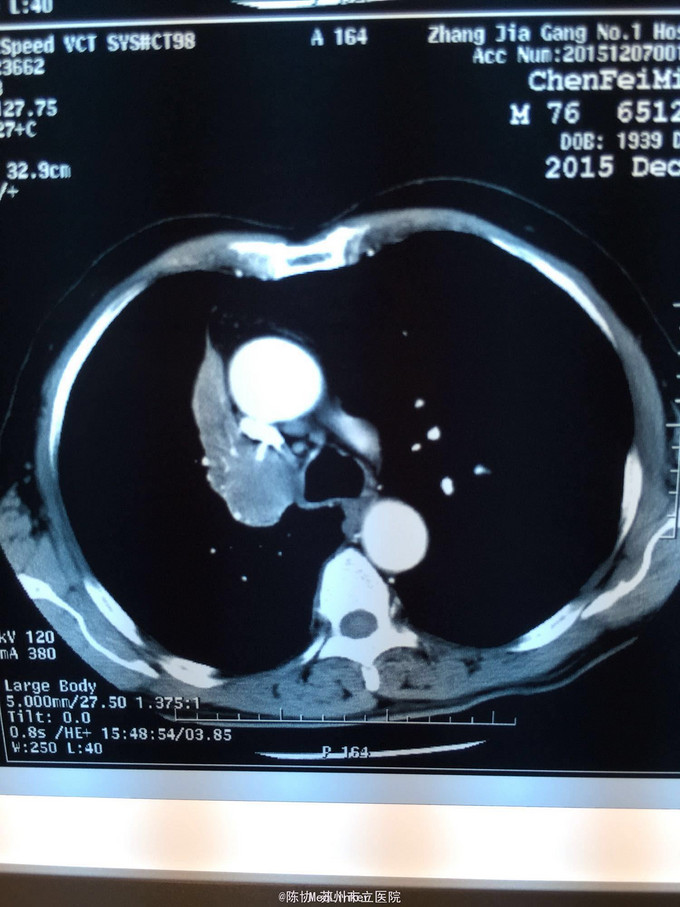

主诉:体检发现右上肺不张半月 77岁男,半月前体检发现右上肺不张,无不适。无消瘦,无咳血,无干咳。去年4月右上肺炎,抗生素治愈,当时CT未见肺肿块。入院支气管镜发现右上支气管开口组织增厚闭塞,开口近侧有隆起约3x3平方毫米,取活检5块病理示中度非典型增生。CT提示在右侧主支气管外侧有30x30平方毫米块影,压迫右上支气管开口处。三大常规和生化检查正常,肿瘤指标正常,TAP正常。

右侧中央型肺癌 重做支气管镜,精于定位找到病症组织,获得病理诊断来指导治疗。 胸外科医生不建议手术,理由是肿瘤位置靠近主支气管和气管,袖状切除不一定看干净。 请问正确的诊断,和比较合理的治疗方法是什么?求助大家思考评论